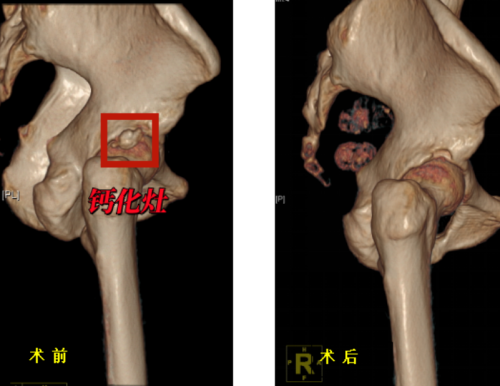

治疗方面,保守疗法包括药物止痛、物理治疗、局部注射等方法。但由于钙化灶的存在,保守治疗往往只能暂时缓解症状,难以彻底解决问题,手术治疗则是更为直接有效的选择。通过关节镜微创技术清除钙化灶,修复受损肌腱。该手术具有创伤小、恢复快、直视下精准操作、清除彻底,效果立竿见影、并发症少,安全性高等优点。

术前、术后三维CT对比示意钙化灶已清除